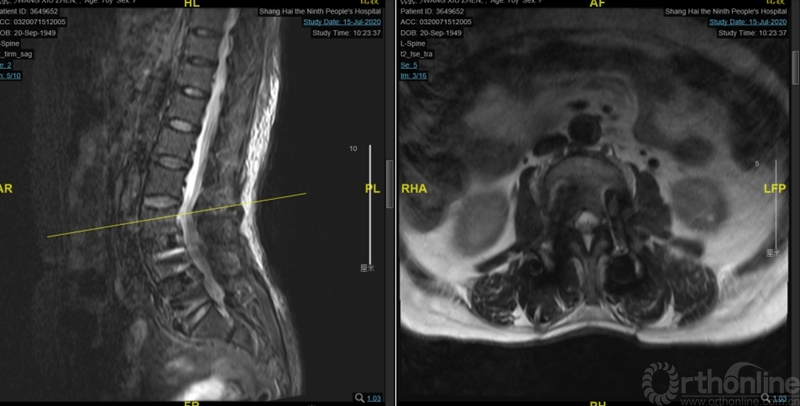

本文提供一例病例,高PI的腰椎显著前凸多节段的腰椎管狭窄症合并腰椎滑脱的患者(PI:57度,LL: 62度,图1、2、3),术前影像显示腰3-4、4-5椎管狭窄、椎体滑脱(图2、3),术前临床表现为右侧下肢麻木无力症状,术中接受了双节段MIS-TLIF手术。

图3:术前核磁:腰3-4、4-5椎管狭窄

术后麻醉清醒后出现急性腰椎管狭窄症状:双足屈伸活动无力伴有麻木,以术前对侧无症状侧的左侧肢体为重。核磁显示:近端减压交界区硬膜囊成角和卡压,硬膜囊向右侧椎管减压侧漂移(图6、7)。

图6:第一次术后核磁:近端减压交界区硬膜囊成角卡压

图7:术后核磁:硬膜囊右侧减压侧椎管漂移